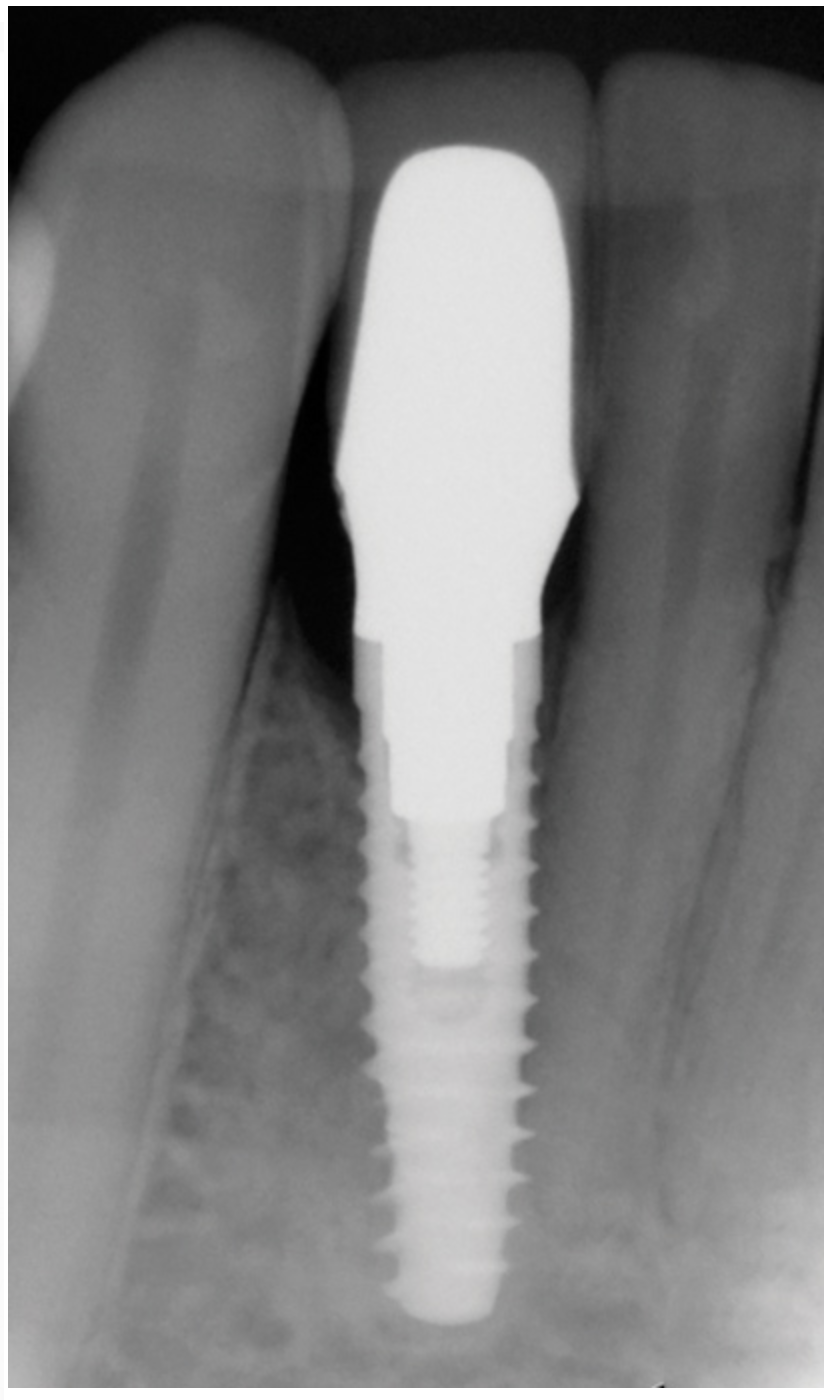

Clinical examination showed 2 mm of buccal recession with a shallow vestibule and absence of keratinized attached gingiva against the crown with 8 mm of circumferential pocketing accompanied by bleeding upon probing (Figure 15 and Figure 16). A periapical radiograph showed a symmetrical vertical osseous defect causing the loss of 50% of the bone around the implant (Figure 17). Because the patient had made a significant investment of time and finances to replace her lost tooth with the implant, she desired that the implant and restoration be retained, if feasible.

Fig 17. Radiograph showed symmetrical infrabony defect affecting 50% of the implant surface.